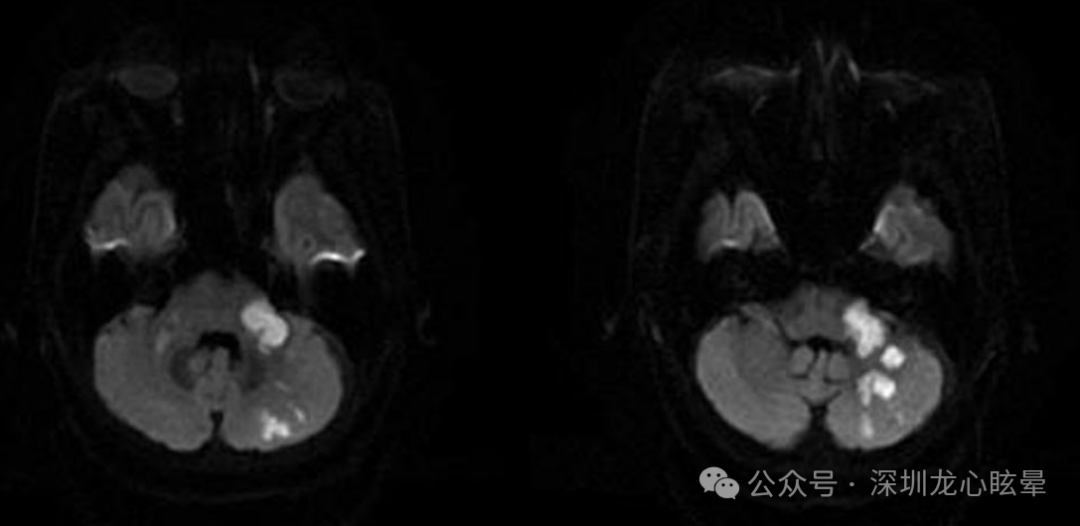

(2)AICA供血区: AICA 为中枢和外周前庭结构(包括迷路、小脑、绒球、脑桥、小脑中脚、延髓)供血。孤立的 AICA梗死大部分是由于基底动脉斑块延伸至 AICA,或小动脉粥样硬化堵塞 AICA 入口所致。AICA 梗死可同时导致中枢和外周前庭病变,前庭神经根入颅处及前庭神经核受累导致的孤立性眩晕(假性前庭神经炎)与前庭外周病变难以鉴别。AICA 区域的梗死较少表现为孤立性眩晕,大多 AICA 受累患者除了眩晕和共济失调,常伴有一侧听力受损及脑干体征,即伴听觉前庭症状的急性脑卒中(acute ischemic stroke with audiovestibular loss , AISwAVL)。AICA梗死最常见自发眼震形式是朝向病灶对侧的水平眼震,部分患者可见类似于布龙眼震(brun’s nystamus)形式的变向性凝视诱发眼震。需要警惕“头脉冲试验-眼震-反向偏斜HINTS三联征”可能无法有效识别AICA病变所致孤立性眩晕。

图7 一例伴听觉前庭症状的急性脑梗死